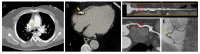

COVID-19 infection often produces cardiovascular complications, which can range from mild to severe and influence the overall prognosis. Imaging is the cornerstone for diagnosing initial COVID-19 cardiovascular involvement as well as treatment guidance. In this review, we present the current state of the literature on this subject while also emphasizing possible algorithms for indicating and executing these investigations.